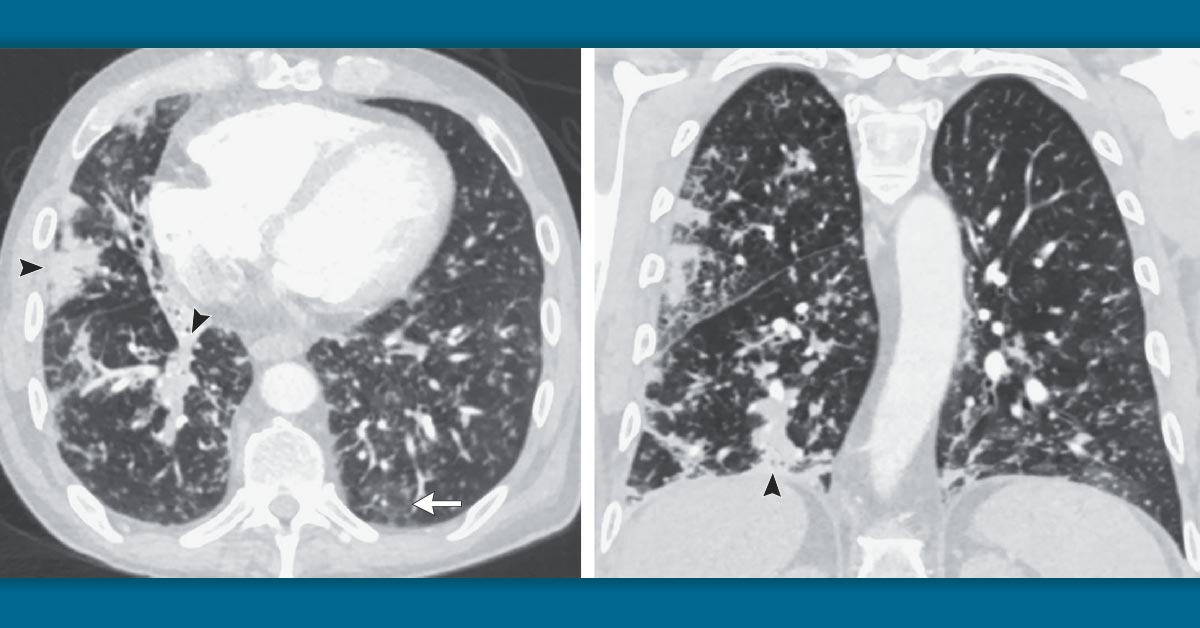

tree in bud nodules

It consists of small centrilobular nodules of soft-tissue attenuation connected to multiple. The tree-in-bud pattern is commonly seen at thin-section computed tomography CT of the lungs. Multiple causes for tree-in-bud TIB opacities have been reported.

The differential for this finding includes malignant. The tree-in-bud sign is a nonspecific imaging finding that implies impaction within bronchioles the smallest airway passages in the lung. The connection to opacified or thickened branching structures extends.

What types of diseases can present with this. 87 rows The tree-in-bud pattern is a special subset of centrilobular nodules initially described. Typically the centrilobular nodules are 2-4 mm in diameter and peripheral within 5 mm of the pleural surface.

The tree-in-bud pattern indicates active and contagious diseases especially those associated with the lungs. The centrilobular nodules have a branching configuration and appear to arise from a stalk otherwise known as a tree-in-bud pattern.